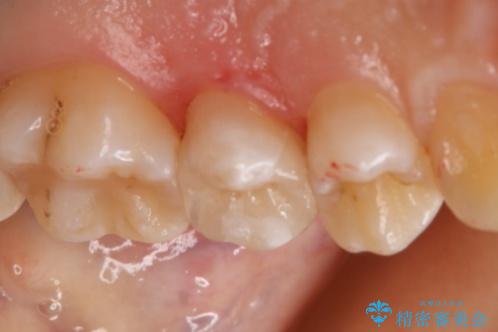

- 左上5番の虫歯治療を主訴に来院された患者様です。

セラミックでの治療を希望されたので形態・切削量を考慮しセラミックインレーでの治療を選択しました。

隣り合っている面(隣接面)は清掃がしづらく虫歯になりやすい場所です。

また、形態の再現が難しいのでインレーなどの補綴物での治療が第一選択となることが多いです。